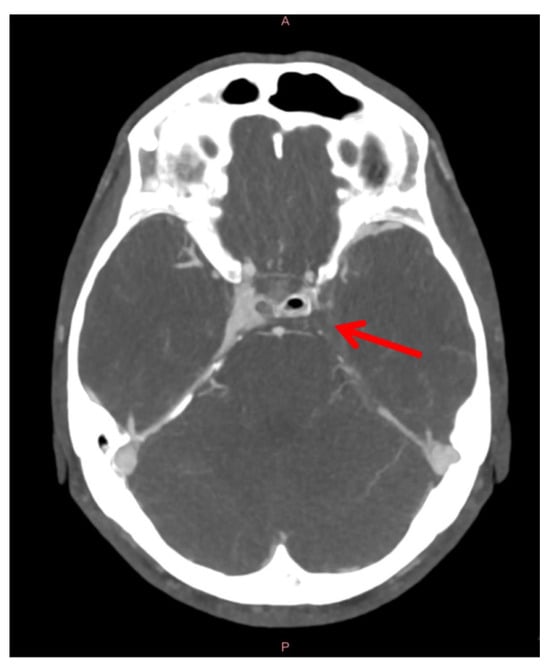

Diagnosis of cavernous sinus thrombosis is radiological, and urgent CT venography of the brain with contrast-enhanced CT of the paranasal sinuses should be performed, which often shows inflammation of the paranasal sinuses and a filling defect of the cavernous sinus. In case of persistent suspicion of cavernous sinus thrombosis or intracranial infection, head MR venography or CT venography is urgently performed, which is the most sensitive method to diagnose thrombosis. A chest X-ray is performed to exclude distant complications (e.g., septic pulmonary thromboembolism) (Figure 8) [].

Figure 8. Head CT venography of a patient with left-sided cavernous sinus thrombosis due to the sphenoid sinusitis. The red arrow indicates a filling void in the left cavernous sinus and the superior petrosal sinus due to the thrombus’s formation.

Septic thrombosis of the cavernous sinus is treated conservatively and surgically. Surgical drainage of the affected paranasal sinuses and orbital decompression in case of elevated intraorbital pressure are performed [,,]. Due to an 11% mortality rate and, in a third of cases, permanent functional visual impairment despite modern management of the disease [], patients are usually admitted to the intensive care unit of the infectious diseases department. In addition to antimicrobial and supportive therapies, anticoagulant therapy with heparin is usually introduced to reduce disease mortality [], although strong supportive evidence for the effectiveness of this therapy is still lacking [,].